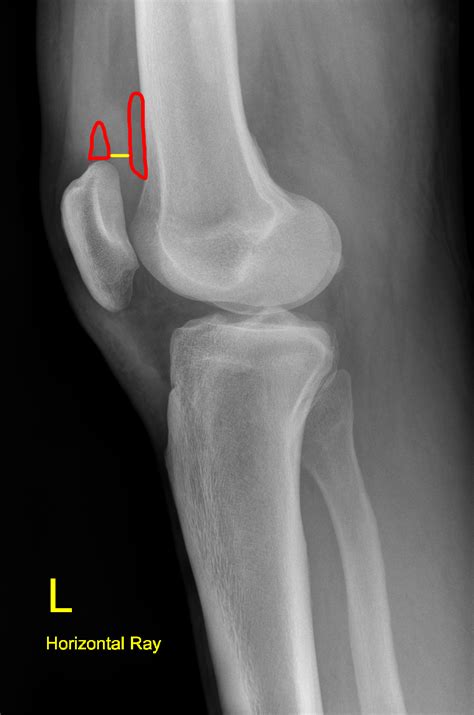

A Lateral Knee Xray is a type of radiographic imaging that captures a side view of the knee joint. This view is essential for evaluating the alignment of the bones, the condition of the joint spaces, and the presence of any abnormalities such as fractures, dislocations, or arthritis. The lateral view complements other views, such as the anteroposterior (AP) and oblique views, to provide a comprehensive assessment of the knee.

• Assessing Alignment: The lateral view helps assess the alignment of the knee joint, which is crucial for diagnosing conditions like patellar dislocation or tibial plateau fractures.

• Detecting Soft Tissue Injuries: While X-rays primarily show bone structures, a lateral view can sometimes reveal soft tissue injuries, such as ligament tears or meniscal damage, by showing indirect signs like joint effusion (swelling).

• Bone Alignment: Ensure that the bones are properly aligned. Any deviation can indicate a fracture or dislocation.

• Soft Tissue Signs: While not always visible, soft tissue injuries can sometimes be inferred from the presence of joint effusion or other indirect signs.